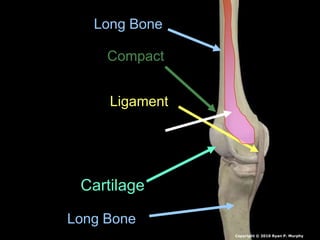

 Bones are held together by connective

 Ligaments: Bones to bones

Copyright © 2010 Ryan P. Murphy

 Tendons: Bones to muscles